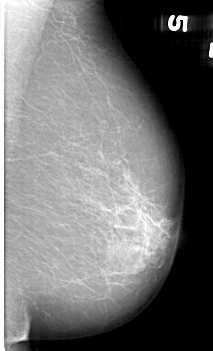

D_4136_1.LEFT_CC

LEFT_CC LINES 5281 PIXELS_PER_LINE 3046 BITS_PER_PIXEL 12 RESOLUTION 43.5 NON_OVERLAY